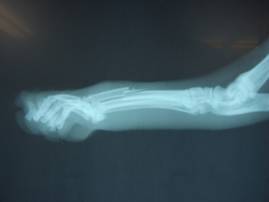

レントゲン検査にて、

右後肢第三中足骨が骨折していることがわかりました。

(右後ろ脚、中指にあたる部分の足の甲)

43-01